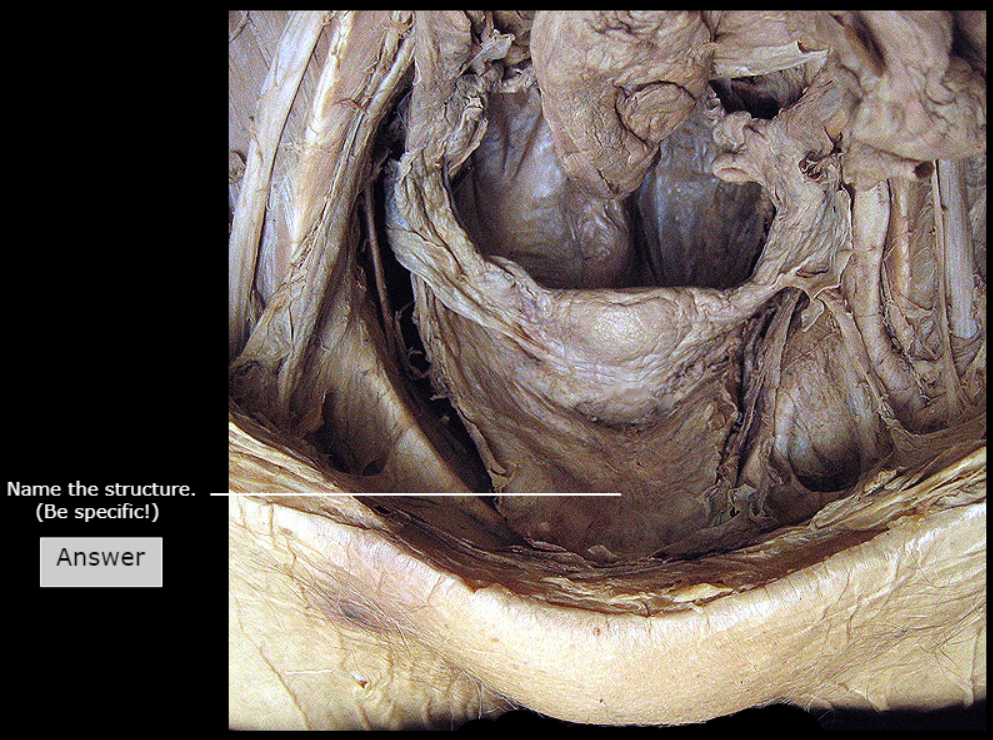

Pubic Symphysis